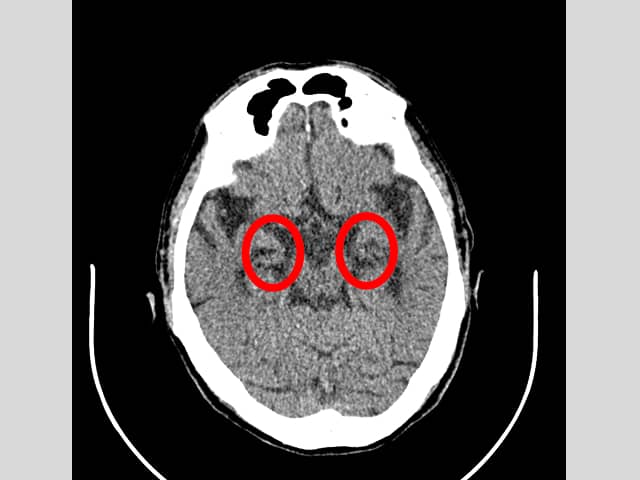

頭部単純CTで認知症に特異的な所見の有無や、脳梗塞、脳出血、硬膜下・硬膜外血腫の有無など調べます。

当日結果説明あり。

※画像提供について、ご本人の了解はいただいております。

両側側頭葉海馬の萎縮を認め、アルツハイマー型認知症に特徴的な所見です。